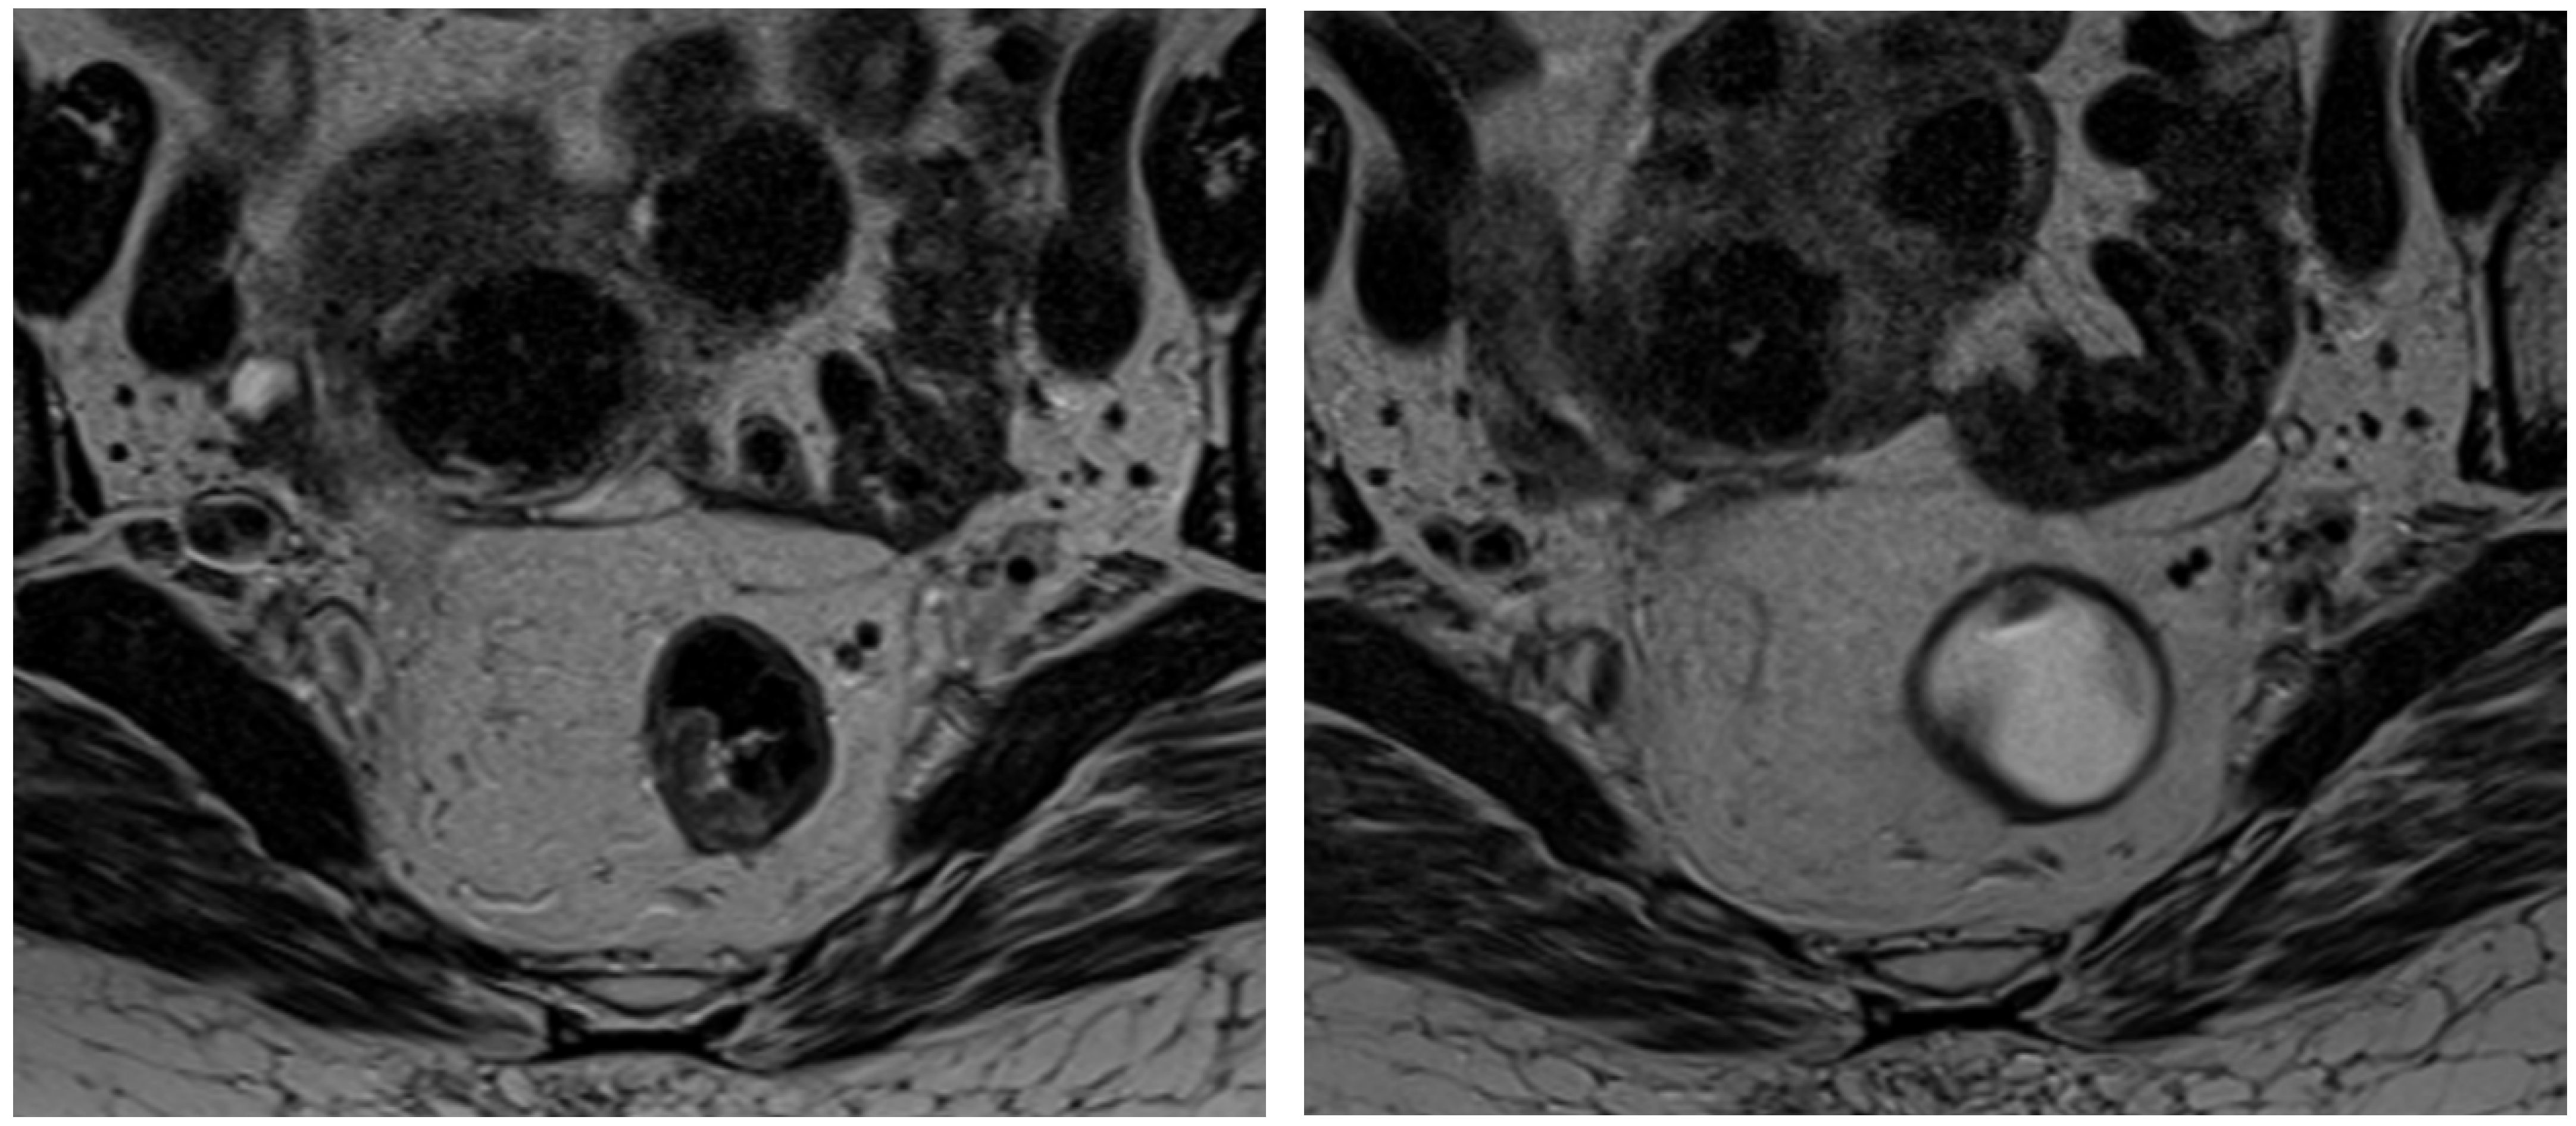

Magnetic resonance imaging (MRI) has become an indispensable tool in managing rectal cancer, particularly for local tumor staging before treatment [12,13,14,15,16]. Its superior imaging capabilities allow for detailed visualization of the tumor and adjacent structures, facilitating a precise assessment of tumor extent and tissue involvement. Moreover, MRI is increasingly utilized in the post-treatment setting for restaging and evaluating the response to neoadjuvant therapy, which is critical for guiding subsequent treatment decisions and optimizing patient outcomes (Figure 1) [17,18].

Figure 1. Staging MRI of rectal cancer before CRT (left image) and follow-up MRI after treatment (right image).